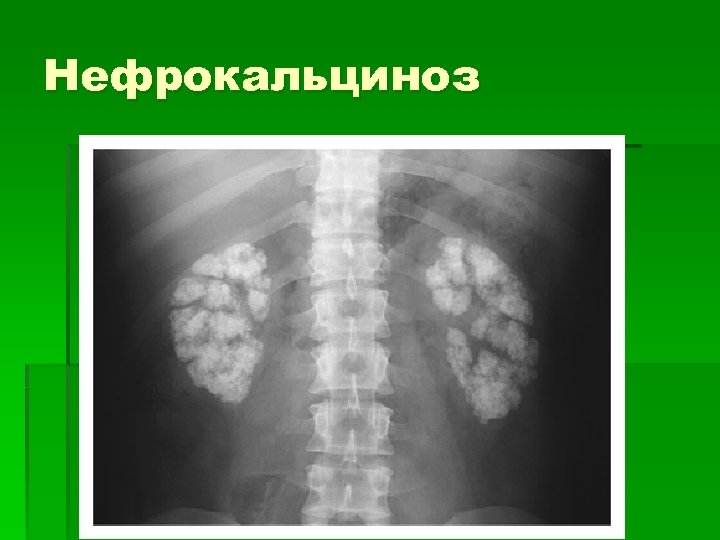

Нефрокальциноз